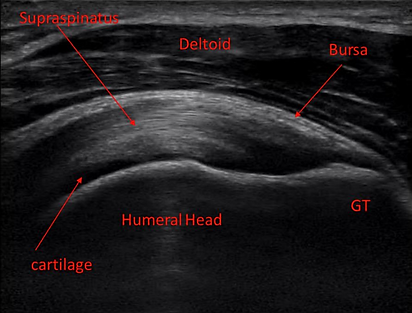

MSK diagnostic ultrasound uses high-frequency sound waves to create detailed images of muscles, tendons, ligaments, joints, and other soft tissues. Unlike X-rays, which primarily show bones, ultrasound focuses on soft tissue structures, making it a valuable tool for evaluating musculoskeletal health.

Joint inflammation, such as bursitis